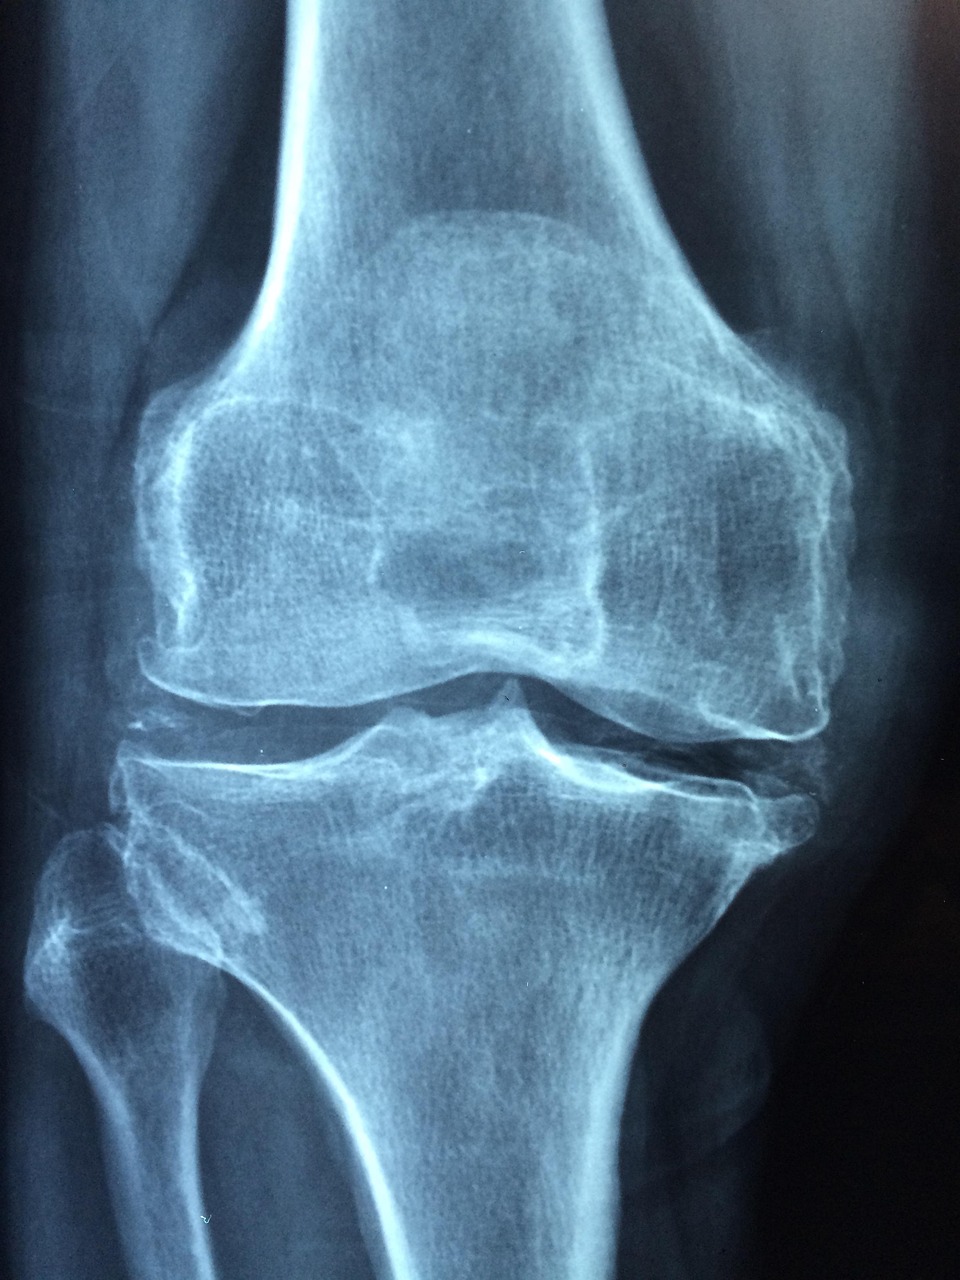

4. 주사치료의 효과와 부작용

4-1. 효과

- 골형성 촉진 및 파골세포 억제 작용

- 골밀도 10~15% 향상 사례도 보고됨

4-2. 부작용

- 근육통, 오심, 발열

- 드물게 턱 괴사(주사 종류에 따라)

- 칼슘 수치 불균형

치료 전 반드시 전문의와 충분히 상담하고 정기검사를 병행해야 합니다.